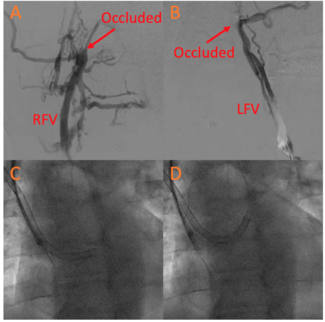

A 56-year-old male presented with a past medical history remarkable for recurrent deep vein thrombosis (DVT) on anticoagulation and cryptogenic stroke. Transesophageal echocardiography with a positive bubble study revealed that he had a large...